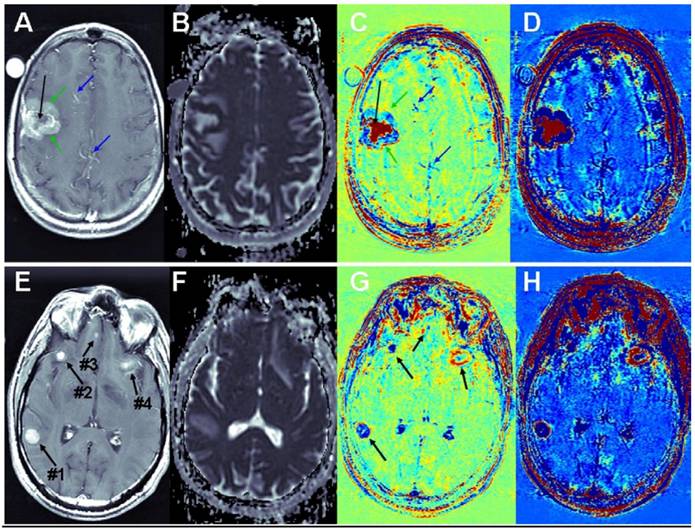

Brain metastases: Examples of T1-MRIs and calculated maps of a brain metastasis are shown in Figure 3, A-D. The apparent diffusion coefficient (ADC) map, calculated from DWMRIs, depicts viable tissues dark and liquefied/necrotic tissues bright. It can be seen that vessels that appear bright in the T1-MRI, appear blue in the subtraction maps. Viable regions in the tumor, which appear enhanced in the T1-MRI and dark in the ADC map, appear blue in the subtraction maps, suggesting fast clearance of the contrast agent. Necrotic regions of the tumor, appearing un-enhanced in the T1-MRI and bright in the ADC map, appear red in the subtraction maps, suggesting high accumulation of the contrast agent. Differentiation between viable and necrotic regions seems similar in the ADC map and in the enhanced subtraction map, while additional information, regarding the clearance rate of the contrast agent within the viable region is depicted in the regular subtraction map. A thin rim of significant contrast accumulation is depicted as a red ring surrounding the blue viable region of the tumor in the subtraction maps.

Figure 3

Contrast-enhanced T1-MRI (A, E) and ADC (B, F), subtraction (C, G) and enhanced subtraction (D, H) maps of patients with breast-cancer (A-D) and melanoma (E-H) brain metastases. Vessels are pointed to by blue arrows, viable regions in the tumor by green arrows and necrotic regions by black arrows.

Int J Biol Sci Image

Additional examples of brain metastases are shown in Figure 3, E-H. In this case, the correlation between BBB leakiness and viability is less clear. Still there are significant variations between the appearances of the different metastases in the subtraction maps, suggesting that the information provided by the BBB maps is not redundant with that of conventional MRI.